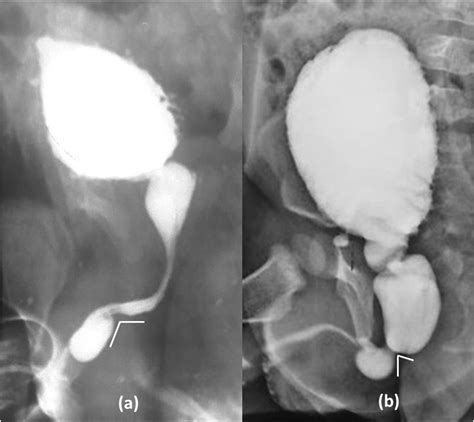

Voiding Cystourethrogram (VCUG) Uses contrast dye to see if the pouch fills during urination.